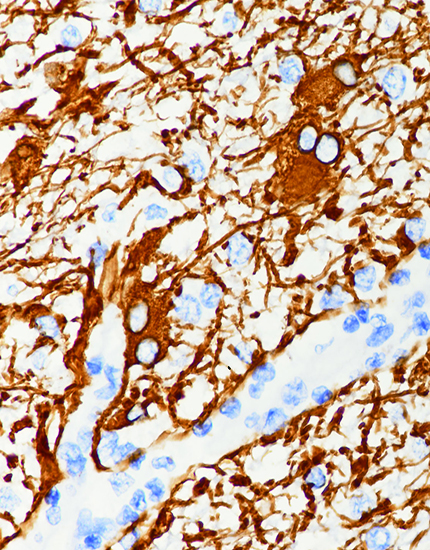

产品名称:GFAP

产品编号:MAB-0769

阳性部位:胞质

图片描述:

脑胶质瘤,GFAP染色,胞质阳性